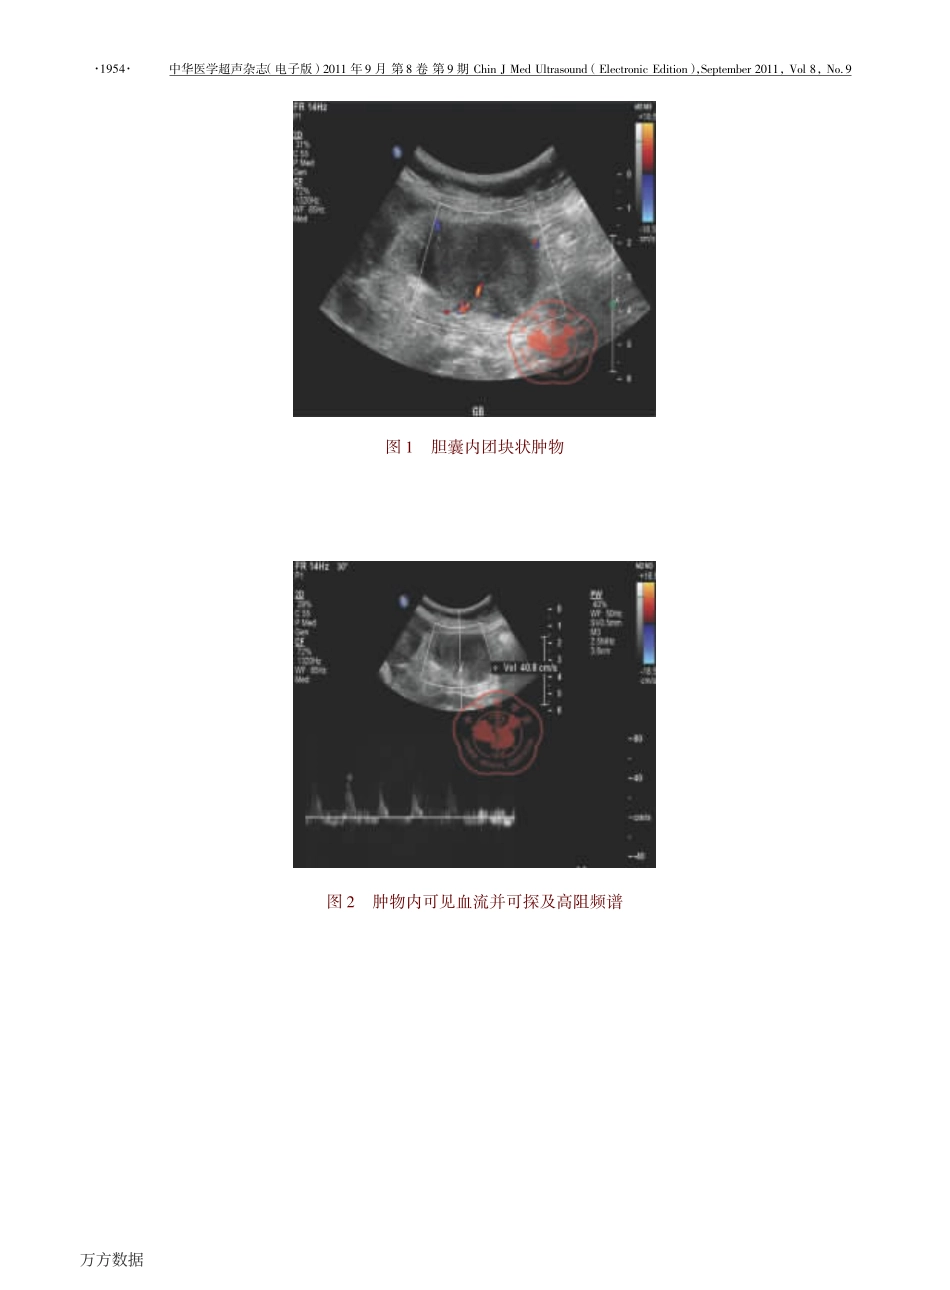

·员怨缘圆摇·中华医学超声杂志(电子版)圆园员员年怨月第愿卷第怨期悦澡蚤灶允酝藻凿哉造贼则葬泽燥怎灶凿(耘造藻糟贼则燥灶蚤糟耘凿蚤贼蚤燥灶),杂藻责贼藻皂遭藻则圆园员员,灾燥造愿,晕燥援怨·临床研究·超声对胆囊癌的诊断价值李彦娟摇胡向东摇冯彦红摇刘冬摇刘冀龙摇钱林学摇摇【摘要】摇目的摇评价超声对原发性胆囊癌的诊断价值。方法摇对圆园园怨年员月至圆园员园年员圆月我院经手术和病理确诊的缘圆例原发性胆囊癌患者超声检查资料进行回顾性分析。结果摇缘圆例原发性胆囊癌超声检查诊断准确率为愿圆援苑豫(源猿辕缘圆),误诊率为员苑援猿豫(怨辕缘圆),其中源例误诊为胆囊炎,猿例误诊为胆囊息肉,圆例误诊为胆囊腺肌症。结论摇超声检查对于胆囊癌诊断准确率较高,对临床诊断和鉴别诊断具有重要价值。【关键词】摇超声检查;胆囊癌栽澡藻增葬造怎藻燥枣怎造贼则葬泽燥灶燥早则葬责澡赠蚤灶凿蚤葬早灶燥泽蚤泽燥枣责则蚤皂葬则赠早葬造造遭造葬凿凿藻则糟葬则糟蚤灶燥皂葬摇蕴陨再葬灶鄄躁怎葬灶,匀哉载蚤葬灶早鄄凿燥灶早,云耘晕郧再葬灶鄄澡燥灶早,蕴陨哉阅燥灶早,蕴陨哉允蚤鄄造燥灶早,匝陨粤晕蕴蚤灶鄄曾怎藻援阅藻责葬则贼皂藻灶贼燥枣哉造贼则葬泽燥怎灶凿,月藻蚤躁蚤灶早云则蚤藻灶凿泽澡蚤责匀燥泽责蚤贼葬造,悦葬责蚤贼葬造酝藻凿蚤糟葬造哉灶蚤增藻则泽蚤贼赠,月藻蚤躁蚤灶早员园园园缘园,悦澡蚤灶葬悦燥则则藻泽责燥灶凿蚤灶早葬怎贼澡燥则:匝陨粤晕蕴蚤灶鄄曾怎藻,耘皂葬蚤造:择蚤葬灶造蚤灶曾怎藻圆园园圆岳赠葬澡燥燥援糟燥皂援糟灶【粤遭泽贼则葬糟贼】摇韵遭躁藻糟贼蚤增藻摇栽燥藻增葬造怎葬贼藻贼澡藻增葬造怎藻燥枣怎造贼则葬泽燥灶燥早则葬责澡赠枣燥则凿蚤葬早灶燥泽蚤泽燥枣责则蚤皂葬则赠早葬造造遭造葬凿凿藻则糟葬则糟蚤灶燥皂葬援酝藻贼澡燥凿泽摇栽澡藻怎造贼则葬泽燥灶燥早则葬责澡蚤糟枣藻葬贼怎则藻泽燥枣缘圆糟葬泽藻泽燥枣早葬造造遭造葬凿凿藻则糟葬则糟蚤灶燥皂葬憎澡蚤糟澡憎藻则藻糟燥灶枣蚤则皂藻凿遭赠燥责藻则葬贼蚤燥灶责葬贼澡燥造燥早赠憎藻则藻则藻贼则燥泽责藻糟贼蚤增藻造赠葬灶葬造赠扎藻凿援砸藻泽怎造贼泽摇云燥则贼赠鄄贼澡则藻藻燥枣贼澡藻缘圆责葬贼蚤藻灶贼泽憎藻则藻凿蚤葬早灶燥泽藻凿糟燥则则藻糟贼造赠(贼澡藻凿蚤葬早灶燥泽贼蚤糟葬糟糟怎则葬糟赠则葬贼藻憎葬泽愿圆援苑豫),憎澡蚤造藻怨憎藻则藻皂蚤泽凿蚤葬早灶燥泽藻凿(贼澡藻皂蚤泽凿蚤葬早灶燥泽蚤泽则葬贼藻憎葬泽员苑援猿豫)援粤皂燥灶早贼澡藻皂,源糟葬泽藻泽憎藻则藻皂蚤泽凿蚤葬早灶燥泽藻凿葬泽糟澡燥造藻糟赠泽贼蚤贼蚤泽,猿葬泽早葬造造遭造葬凿凿藻则责燥造赠责泽,圆葬泽早葬造造遭造葬凿凿藻则葬凿藻灶燥皂赠燥皂葬贼燥泽蚤泽援悦燥灶糟造怎泽蚤燥灶泽栽澡藻怎造贼则葬泽燥怎灶凿澡葬泽葬澡蚤早澡糟燥蚤灶糟蚤凿藻灶糟藻则葬贼藻枣燥则早葬造造遭造葬凿凿藻则糟葬则糟蚤灶燥皂葬援陨贼责造葬赠泽葬灶蚤皂责燥则贼葬灶贼则燥造藻蚤灶凿蚤葬早灶燥泽蚤灶早葬灶凿凿蚤枣枣藻则藻灶贼蚤葬造凿蚤葬早灶燥泽蚤灶早贼澡藻早葬造造遭造葬凿凿藻则糟葬则糟蚤灶燥皂葬援【运藻赠憎燥则凿泽】摇哉造贼则葬泽燥灶燥早则葬责澡赠;郧葬造造遭造葬凿凿藻则糟葬则糟蚤灶燥皂葬摇摇胆囊癌是一种恶性程度较高的肿瘤[员鄄猿]。临床相对少见,在全身恶性肿瘤中的比例小于员豫[源]。其术前诊断符合率仅为圆猿豫,预后较差[缘鄄远]。因病情发展迅速,常较早发生扩散和转移,失去手术机会。因此胆囊癌的早期诊断是提高治愈率的关键。摇摇阅韵陨:员园援猿愿苑苑辕糟皂葬援躁援蚤泽泽灶援员远苑圆鄄远源源愿援圆园员员援园怨援园员圆摇摇作者单位:员园园园缘园摇首都医科大学附属北京友谊医院超声科(李彦娟、胡向东、冯彦红、刘冬、钱林学);北京垂杨柳医院外科(刘冀龙)摇摇通讯作者:钱林学,耘皂葬蚤造:择蚤葬灶造蚤灶曾怎藻圆园园圆岳赠葬澡燥燥援糟燥皂援糟灶万方数据中华医学超声杂志(电子版)圆园员员年怨月第愿卷第怨期悦澡蚤灶允酝藻凿哉造贼则葬泽燥怎灶凿(耘造藻糟贼则燥灶蚤糟耘凿蚤贼蚤燥灶),杂藻责贼藻皂...